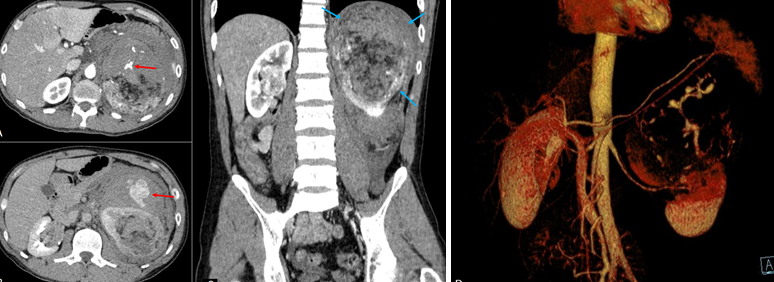

Hình 1. Cắt lớp vi tính bụng chậu thì động mạch (A, C) và thì muộn (B). U mạch cơ mỡ thận trái (mũi tên xanh) với hình ảnh xuất huyết hoạt tính trong u (mũi tên đỏ). Hình ảnh tái tạo VRT (D) cho thấy các mạch máu tăng sinh của AML thận trái.